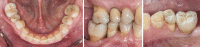

Figures